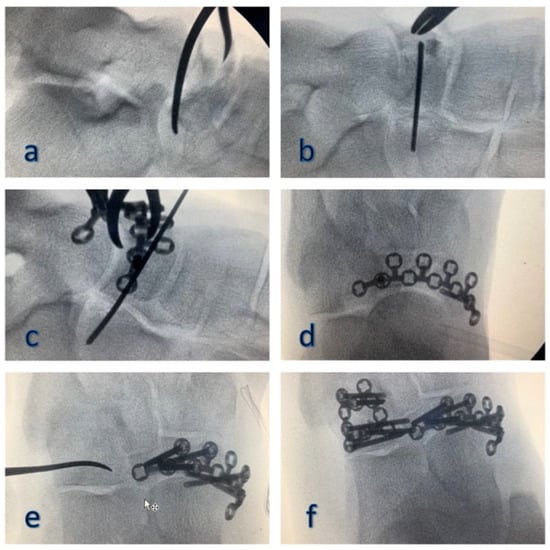

3. Surgical Procedure